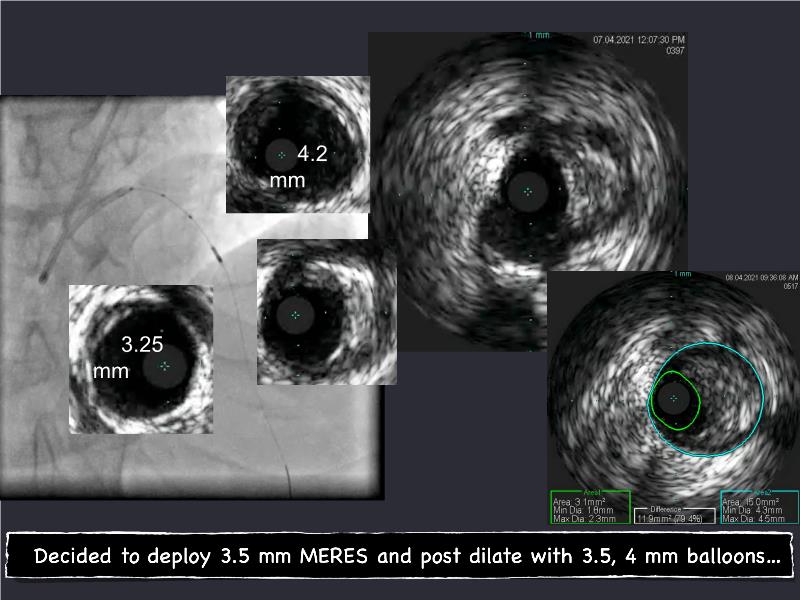

- To understand novel tools and techniques for effective management of bifurcation lesions and long diffused lesions using dedicated stenting solutions